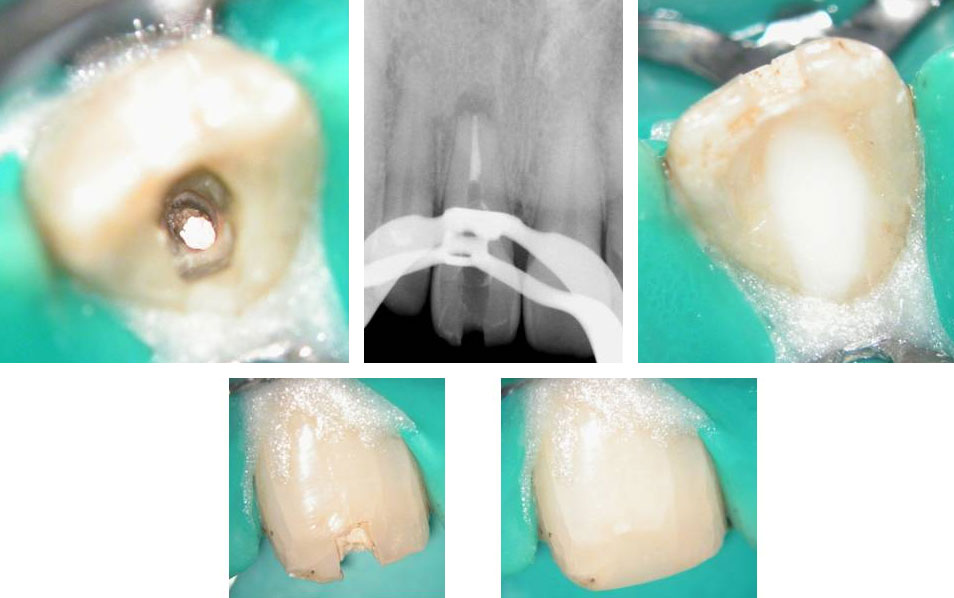

Central incisor referred after previous clinician had accessed the tooth and was unable to locate the calcified canal.

Removal of temporary restoration shows palatal perforation (red arrow) and a calcified canal in the middle (yellow arrow)

Palatal perforation was supra-crestal and was repaired with GIC

Calcified canal located

Calcium hydroxide placed

Recall after 10 days. Sinus tract healed

Post-op & 1 year recall